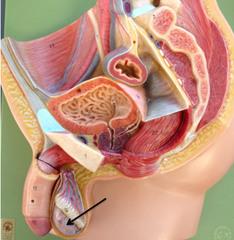

Bulbourethral gland (male)

Cervix

Clitoris

Corpora cavernosa (pl.) Corpus Cavernosum (s.)

Corpus Spongiosum

Ejaculatory Duct

Epididymis

External urethral orifice (male)

External urethral orifice (female)

Glans penis

Labia majora/minora

arrow

Prostate gland

Prostatic/spongy urethra (males)

Scrotum

Seminal vesicle

Seminiferous tubule

Testis (s.) Testes (pl.)

Ureter

Urethra

Urinary Bladder (male)

Urinary Bladder (female)

Uterine (=fallopian) tube

Uterus

Vagina

Vaginal orifice

Vas deferens (=ductus deferens)